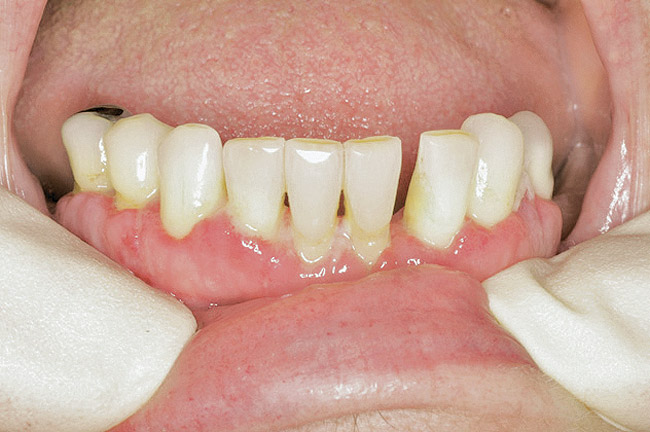

Figure 2  Post-metastatic cancer patient with BRONJ in the lower right quadrant and in the lower left quadrant.

Figure 2

Figure 3  Post-metastatic cancer patient with BRONJ in the lower right quadrant and in the lower left quadrant.

Figure 3

For patients on IV bisphosphonates, after bone is exposed, it is almost impossible to cover.15 Most cases worsen if surgical intervention is performed. Most patients must simply deal with the exposed bone and keep it clean so that bacterial infection does not occur. Figure 2 and Figure 3 show a postmetastatic prostate cancer patient with exposed bone. The treatment plan for this patient was to make a soft-lined denture that would not put pressure on the exposed bone and to check for bacterial infection on a routine basis.